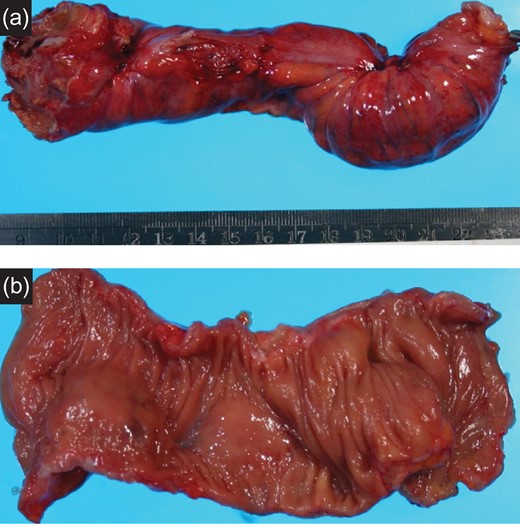

Specimen: Strong dimpling of the serosa on rectum and ileocecum was recognized (Figs 3a, b and 4a, b).

(a) Resected specimen (rectum): The serosal dimpling was observed. (b) Resected specimen (rectum): A SMT-like lesion was observed.

(a) Resected specimen (ileocecum): Serosal dimpling was also observed. (b) Resected specimen (ileocecum): A SMT-like lesion was also observed.